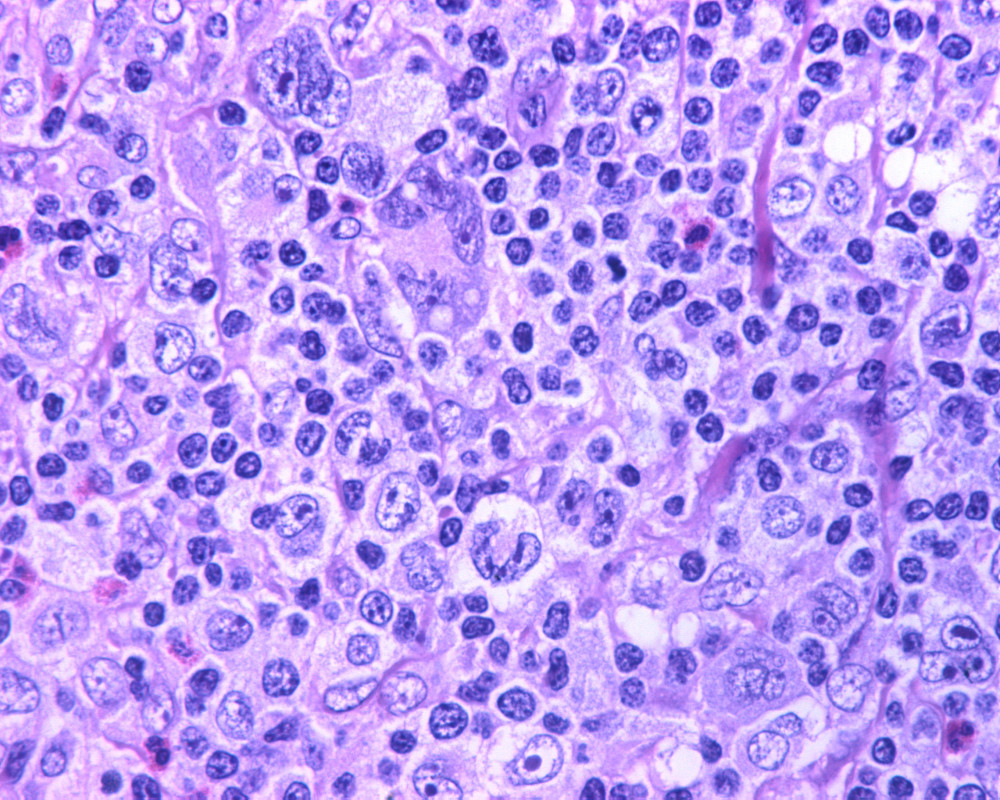

Biopsia de ganglio linfático.

-¿Cuál es su diagnóstico de trabajo por morfología y su diferencial?

DIAGNÓSTICO: LINFOMA DE HODGKIN CLASICO, ESCLEROSIS NODULAR, VARIANTE SINCICIAL